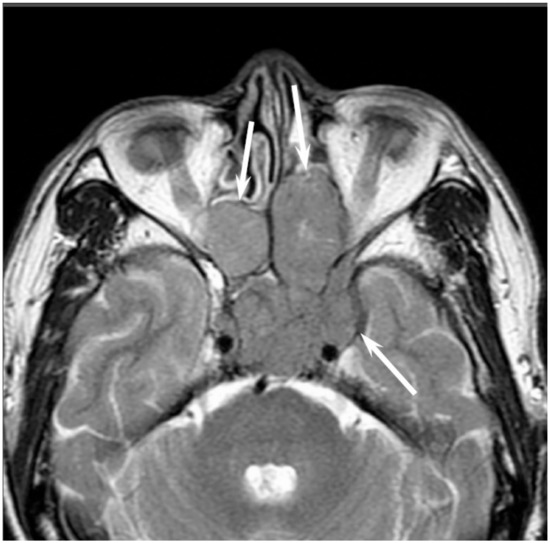

On CT, sinonasal lymphomas frequently show both infiltrative or permeative bony invasion and exhibit varying degrees of regional bony destruction [12]. NHLs with permeative-type tumor invasion typically cross the sinus wall and exhibit remnants of sinus wall as a linear structure within the tumor (Figure 5) [24]. In contrast, bony resorption or remodeling caused by the lymphoma may also be accompanied by bone sclerosis [25]. NHLs usually show isointensity on T1WI and slightly hyperintensity on T2WI [11]. Although the signal intensity of NHLs is nonspecific, the ADC measurement helps differentiate these tumors from other malignancies. In the maxillary sinus, the ADC values of NHL (0.61 × 10−3 mm2/s) were shown to be lower than those of SCCs (0.95 × 10−3 mm2/s), which reflects the greater cellularity of NHLs [12]. Although NHLs usually appear as a homogeneously enhanced mass, necrotic areas within the tumor are occasionally observed in NK/T-cell lymphoma [26,27].

Figure 5. Diffuse large B-cell lymphoma of the left maxillary sinus. Contrast-enhanced CT image showing a homogeneously enhanced lesion accompanied by remaining sinus walls as a linear structure within the tumor (arrows).